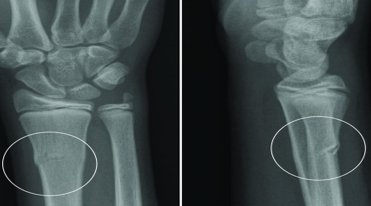

Buckle Fracture

Raised or bulging projection at the site

Seen in the wrist, typically from a fall on an outstretched hand (FOOSH).